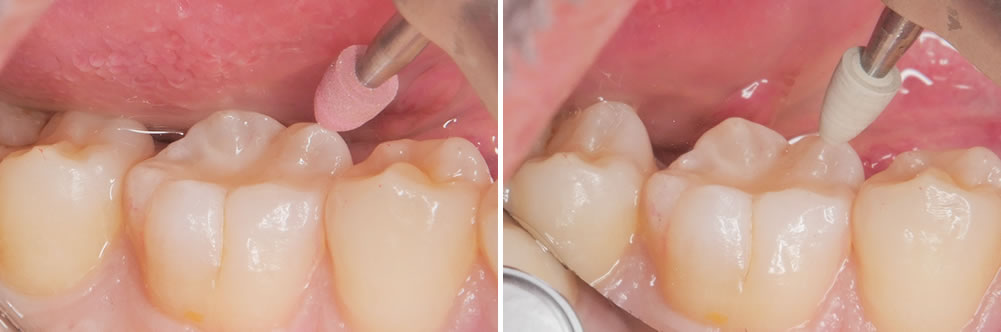

接着処理

酸処理後には接着処理を行います。

CR充填

コンポジットレジンという樹脂の材料を用いて削った部分を埋めていきます。

形態を整えて歯の形にしていきます。